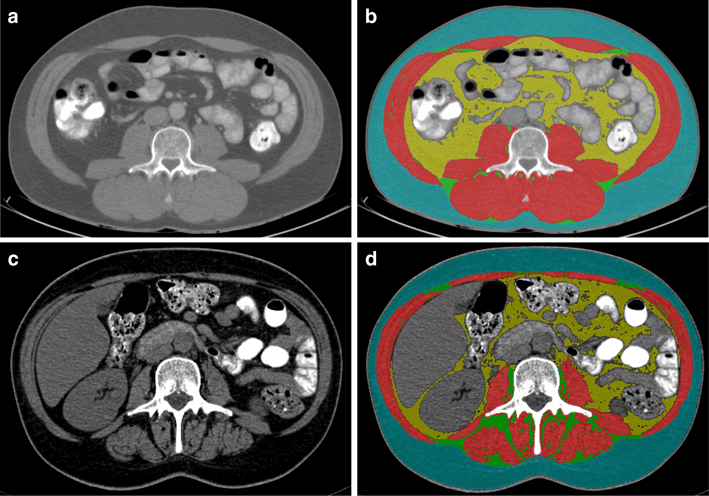

CT scans routinely taken at CRC diagnosis for diagnostic and staging purposes were obtained from medical records and used to quantify adipose and muscle tissue parameters (Fig. 2) [17, 31, 32]. CT scans taken more than 3 months after start of initial treatment were excluded (Fig. 1), as these were deemed to be unrepresentative of body composition at CRC diagnosis. The majority of included CT scans were taken before start of initial treatment (93%; range 0–185 days before start of treatment; 7% post-treatment; 4–36 days after start of treatment). According to published standard procedures [17, 31], the CT image at the level of the third lumbar vertebra (L3) was selected and analyzed with Slice-O-Matic software (version 5.0, TomoVision, Canada). It has been shown previously that cross-sectional areas of muscle and visceral fat tissue at a single cross-sectional image at the level of L3 correlate highly with total body muscle mass (Pearson’s r = 0.92) [44] and visceral fat volume (0.95 in men, 0.94 in women) [45], respectively. Relevant tissues were identified based on their anatomical features and the level of radiodensity in Hounsfield units (HU). The following HU ranges were applied: visceral adipose tissue, −150 to −50 HU; subcutaneous adipose tissue, −190 to −30 HU; intermuscular adipose tissue, −190 to −30 HU; and skeletal muscle, −29 to +150 HU [17]. The total cross-sectional area of visceral and intermuscular adipose tissue, and skeletal muscle was determined (cm2). The area of subcutaneous adipose tissue was not included in the analyses as this tissue was not fully visible (i.e., cutoff) in a substantial proportion of CT images (27%). CT image analyses were performed by two trained raters (MtM, MB). Intra-rater analyses showed excellent reproducibility for quantifying muscle and adipose tissues (absolute agreement type intraclass correlations: 1.00 for 9% duplicate analyses).

Fig. 2

Computed tomography (CT) images showing the measurement of skeletal muscle and different types of adipose tissue at the level of the third lumbar vertebra (L3); a and b show the original and tagged (i.e., colored) CT images, respectively, of one included CRC survivor [man, 50 years old at CRC diagnosis, self-reported body mass index (BMI) at diagnosis: 27.6 kg/m2] with a relatively high skeletal muscle index (67.0 cm2/m2); area of visceral adipose tissue and intermuscular adipose tissue: 118.3 and 10.1 cm2, respectively; mean muscle attenuation: 35.9 Hounsfield units (HU); c and d show the original and tagged CT images, respectively, of one included CRC survivor (woman, 49 years old at CRC diagnosis, BMI at diagnosis: 21.0) with a relatively low skeletal muscle index (30.8 cm2/m2); area of visceral adipose tissue and intermuscular adipose tissue: 52.9 and 20.4 cm2, respectively; mean muscle attenuation: 27.2 HU. Within the tagged figure, yellow represents visceral adipose tissue; blue represents subcutaneous adipose tissue; green represents intermuscular adipose tissue; and red represents skeletal muscle. (Color figure online)